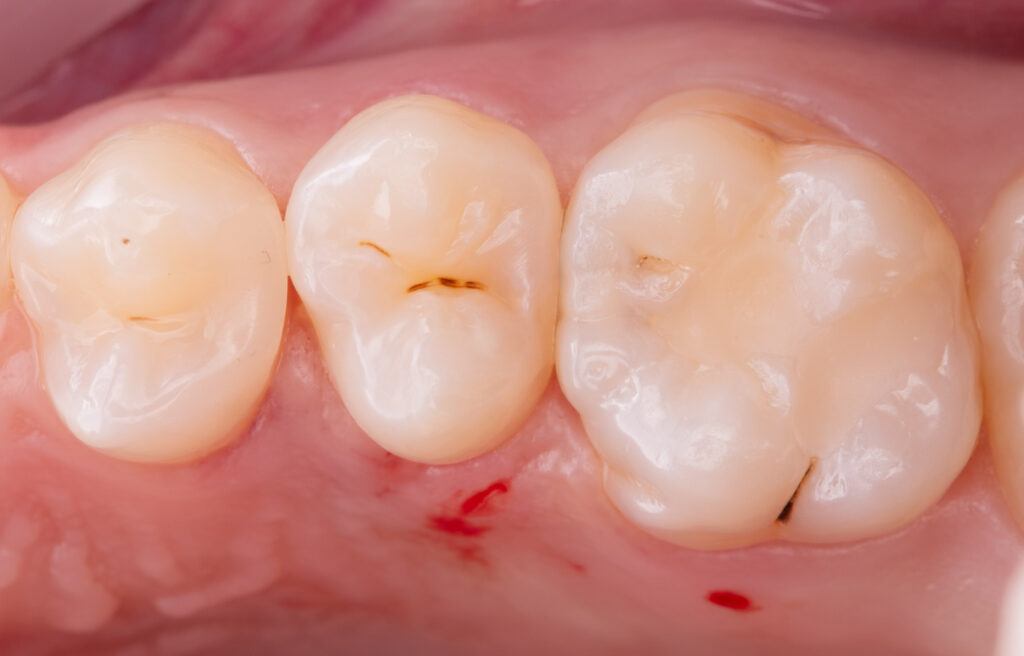

Treatment of caries on tooth 1.6 with preservation of proximal contact on the crista transversa and restoration of the secondary tooth anatomy.

The composite materials applied were: Asteria A2B for wall reconstruction, EvoCeram Dentin 2 as an opaque dentin composite, NeoSpectrum A2 for anatomical modeling, and Enamel brown stain for characterization.

Total treatment time: 1 hour.